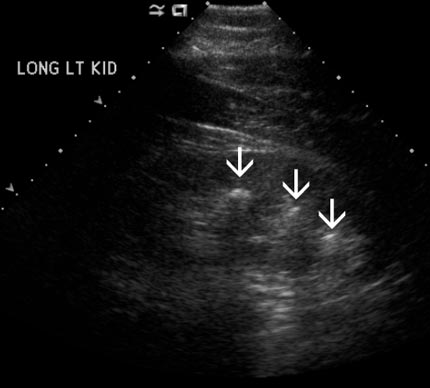

Hay visibles tres piedras nefríticas (flechas) en el riñón derecho. Ninguna de ellas está causando una obstrucción (bloqueo).

Nota: Las imágenes se muestra para fines ilustrativos. No trate de sacar conclusiones comparando esta imagen con otras en el sitio. Solamente los radiólogos calificados deben interpretar las imágenes.